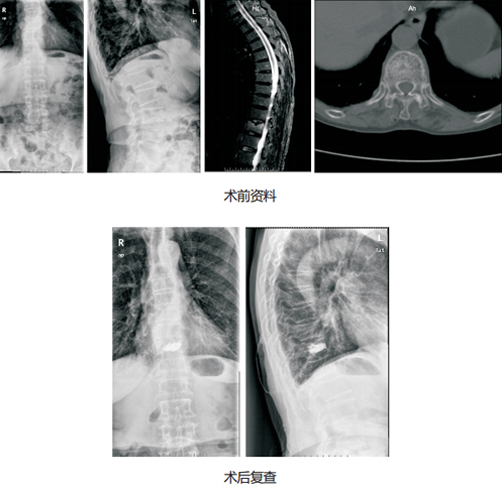

对于胸腰椎骨质疏松压缩性骨折,早期行微创手术治疗是治疗的最佳方法,椎间盘中心目前开展较成熟的微创手术主要包括经皮椎体成形术 ( PVP) 和经皮后凸成形术(PKP)。这两种微创手术是通过穿刺针,在压缩的骨折椎体内注入骨水泥,术后可以达到稳定骨折、恢复椎体力学强度、防止椎体进一步压缩和缓解疼痛,使患者早期恢复正常活动。

技术优势:1.微创、局麻下操作,出血少、更安全。2.稳定骨折、缓解疼痛,恢复快,术后24h早期下床活动,避免卧床并发症。